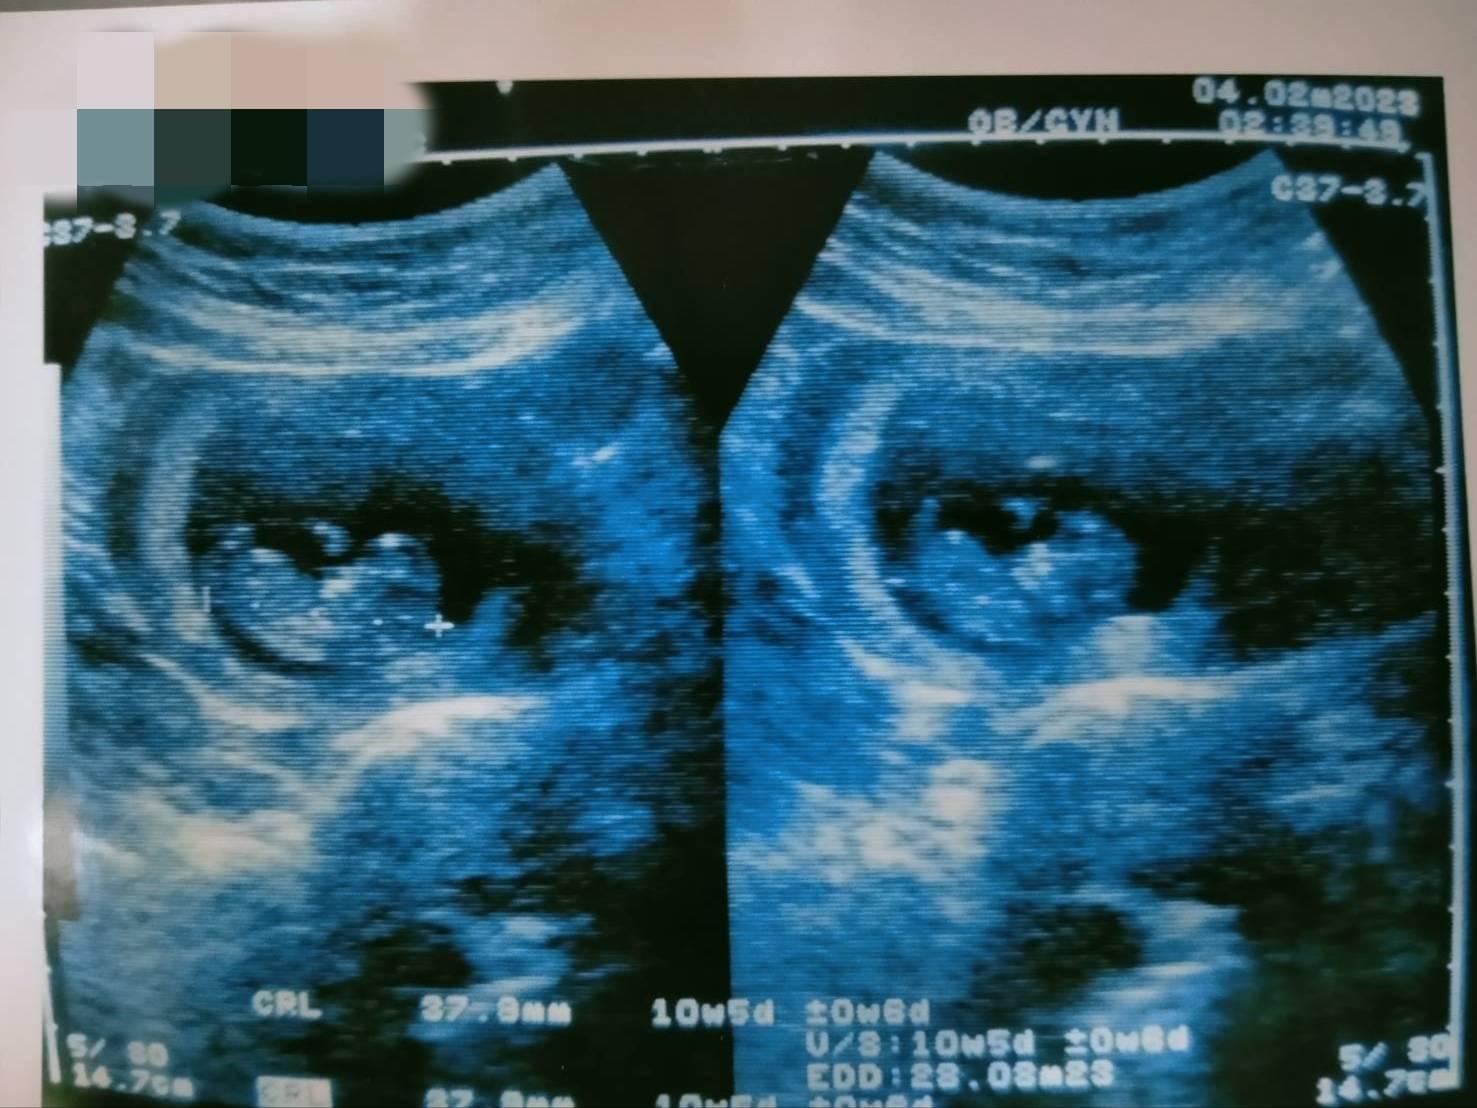

รูปอัลตราซาวน์แบบนี่อายุครรภ์กี่เดือน

คือเจ้าตัวบอกครับ 4 เดือน แต่เปรียบเทียบจากภาพในอินเทอร์เน็ต เหมือนจะ 2 เดือน

และข้อความในบัตรฝากครรภ์ หมายถึงอะไรบ้างครับ

ช่วยคำนวณวันที่เริ่มตั้งครรภ์ให้หน่อยครับ ในฟิล์มอัลตร้าซาวน์ มีข้อมูลตามนี้ วันที่เข้ารับการตรวจ 10/2/2023 ตั้งครรภ์มา 10 week 5 day +- 5 day กำหนดการคลอด 28 / 8 / 2023 ดูรูปได้จากกระทู้เก่าผมได้ค